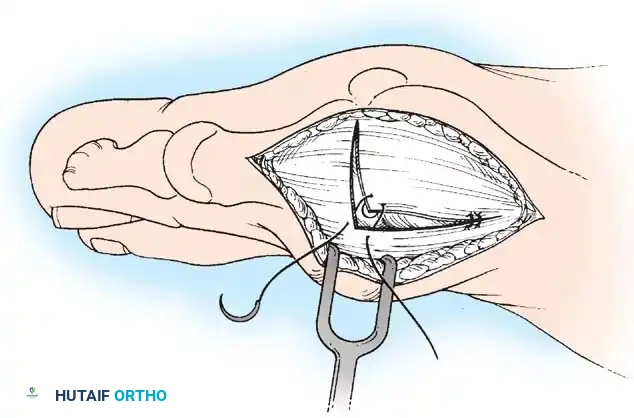

Modifi ed McBride Bunionectomy TECHNIQUE 78-1

SKIN AND CAPSULAR INCISION

• With the patient supine and a tourniquet on the limb, extend a midline, straight, medial incision from the middle of the proximal phalanx to 2 cm proximal to the junction of the medial eminence with the metatarsal shaft (Fig. 78-13). This incision usually is in an internervous plane between the most medial branches of the superfi cial peroneal nerve dorsally and the medial proper digital branch of the medial plantar nerve plantarward. (McBride recommended a single incision beginning at the fi rst web space and extending proximally and medially across the metatarsal, ending on the medial side of the fi rst metatarsal proximal to the exostosis.)

• Make a longitudinal capsular incision (the original McBride capsular incision was transverse) 3 to 4 mm plantar to the line of the skin incision (Fig. 78-14).

Modifi ed McBride Bunionectomy TECHNIQUE 78-1—cont’d

• By sharp dissection, raise the periosteum and the capsule dorsally and plantarward from the base of the proximal phalanx to the proximal edge of the medial eminence (Fig. 78-15). At the proximal end of the medial eminence, avoid releasing the proximal bony attachments of the medial capsule on the metatarsal neck (especially in the dorsal direction) in an attempt to expose the medial eminence. To ensure adequate exposure without disruption of this proximal attachment, a longitudinal capsular incision is suggested.

• Elevate the capsule by sharp dissection dorsalward and plantarward to expose the dorsal aspect of the metatarsal head, the entire medial eminence, and the plantar plate. A periosteal elevator is not recommended because of the possibility that the proximal attachments of the capsule may be released.

L-SHAPED CAPSULAR INCISION

• Alternatively, make the capsular incision in an inverted L shape (Fig. 78-16A).

• Raise the dorsal fl ap deep to the nerve and veins until the accessory slip of the extensor hallucis longus tendon is seen in the proximal portion of the incision where it is easier to identify. The tendon almost always can be located with careful searching. If it is not seen at the dorsomedial aspect of the fi rst metatarsal, however, begin the longitudinal limb of the incision at this slope of the metatarsal from dorsal to medial.

• Begin the incision proximally on the dorsomedial side of the fi rst metatarsal shaft and 2 to 3 mm medial to the accessory slip of the extensor hallucis longus tendon. Carry the incision to the bone at the level of the fi rst metatarsal joint, extending proximally 4 to 6 cm.

• Make the transverse limb of the capsular incision at the level of the joint, stopping 2 to 3 mm from the tibial sesamoid bone; this limb transects the capsular insertion of the abductor hallucis muscle (Fig. 78-16B and C).

Fig. 78-15 Modifi ed McBride procedure. Capsule is opened, and attachment of capsule on metatarsal neck (arrow) is carefully preserved.

• Beginning on the plantar aspect of the incision, remove the capsule from the medial eminence from the inside out. Avoid buttonholing the capsule at the junction of the medial eminence and the metatarsal by directing the small-bladed knife down the slope of the eminence.

• Free the capsule subperiosteally on its dorsomedial surface, and retract it proximally and plantarward (Fig. 78-16D).

• Insert one small Hohmann retractor over the dorsolateral surface of the metatarsal head and another beneath the head at the head and neck junction, while distracting and plantar fl exing the hallux to expose the articular surface of the metatarsal head for evaluation of its condition and orientation. Reduce the hallux congruently on the metatarsal head.

• If the hallux is in more than 15 degrees of valgus after reduction, a distal metatarsal osteotomy is needed.

MEDIAL EMINENCE REMOVAL

• After inspecting the metatarsophalangeal joint for degenerative changes, loose bodies, or synovial abnormalities, remove the medial eminence by fi rst scoring with an osteotome its proximal edge where the eminence meets the shaft. Always consult the preoperative radiographs to determine how much of the medial eminence should be removed.

• Using the same osteotome or a power saw, begin the exostectomy distally at the parasagittal groove, and direct it medially toward the scored area on the metatarsal shaft (Fig. 7817). If a power saw is used, a 9-mm blade, rather than a 4to 5mm blade, is preferred. The medial direction of the osteotomy prevents splitting of the metatarsal shaft, especially if the proximal edge of the osteotomy has been scored as recommended.

• After the medial eminence has been removed, use a small rongeur to round off the dorsal and plantar edges of the medial aspect of the metatarsal head. Rasping the raw bone concludes the initial stage of the procedure. Use bone wax on the raw surfaces of bone of the metatarsal head.

ADDUCTOR TENDON AND LATERAL CAPSULAR RELEASE

• Begin the second stage with a dorsal longitudinal incision beginning 2 to 3 mm proximal to the dorsal aspect of the fi rst web space to avoid web contracture postoperatively; extend it proximally between the fi rst and second metatarsal heads for 3 to 4 cm (Fig. 78-18). This allows adequate exposure of the adductor insertion into the base of the proximal phalanx, the lateral head of the fl exor hallucis brevis muscle converging on the fi bular sesamoid, and the entire lateral capsule from the extensor hallucis longus muscle to the plantar plate.